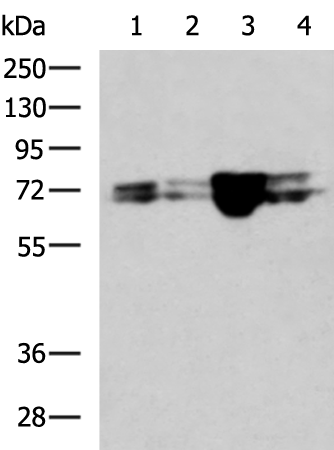

分类: 科研抗体货号: P07407别名: FLA10; KLP-20应用: WB,IHC反应种属: Human, Mouse

分类: 科研抗体货号: P07423别名: LRP, VAULT1应用: WB,IHC反应种属: Human, Mouse, Rat